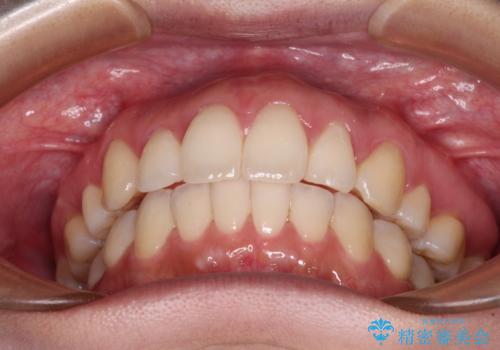

再矯正で突出した口元を引っ込める 抜歯矯正の後戻り

- 抜歯矯正の後戻りで前歯が突出してきていることを気にして来院された患者様です。

口元の突出感を改善するにあたり、抜歯矯正は行うことができないため、奥歯の後方移動とIPR(歯と歯の間を削る)により達成することとしました。

再度後戻りしたときに対応しやすいよう、インビザラインにて矯正治療を行うこととしました。

しっかりと装着時間を守り、ゴムかけにも協力していただいたので、口元を引っ込めることができました。